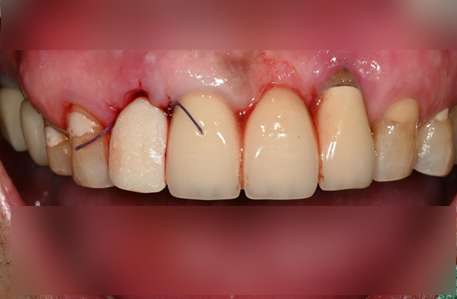

뼈가 부족할 때는 골유도재생술(GBR)이라는 고난도 기법을 사용합니다.

단순히 인공뼈를 채워 넣는 것이 아니라, 뼈가 잘 차오를 수 있도록 특수 차폐막을 덮어주는 정교한 과정이 필요합니다.

• 인공뼈 이식: 환자 본인의 뼈(자가골)나 검증된 인공뼈를 이식합니다.

• 차폐막 활용: 잇몸 세포가 뼈가 자랄 공간을 방해하지 못하도록 막아주어, 단단한 뼈가 형성될 시간을 벌어줍니다.

• 상악동 거상술: 위턱 어금니 부위의 뼈가 얇을 때는 공기주머니(상악동)를 들어 올려 뼈를 채우는 특수 수술을 병행합니다.